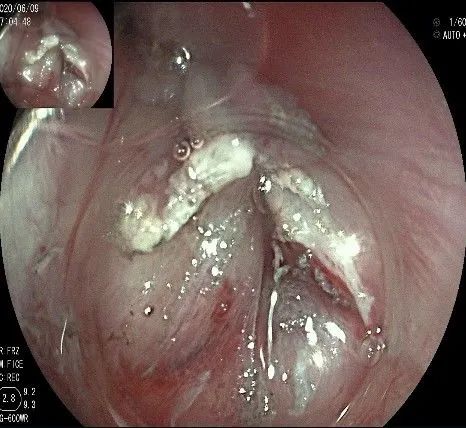

沿切开的边缘,从口侧开始向下进行粘膜下剥离,剥离的间隙是瘤体之上粘膜之下,期间反复进行粘膜下注射。

随着剥离的进行,瘤体与周围组织的关系越来越清晰。